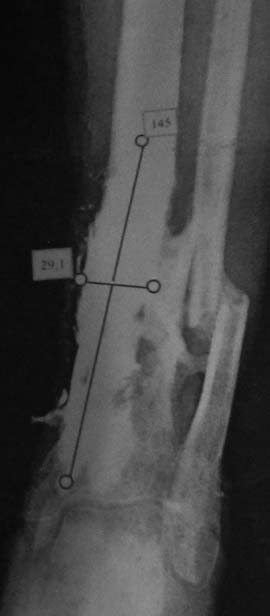

Хронический остеомиелит н/3 б/берцовой кости+атрофичный ложный сустав в/3 б/берцовой кости

Мужчина, 50 лет. Травма в результате ДТП в сентябре 2012 года. Сочетанная травма. ЗЧМТ. Ушиб головного мозга. З/переломы 5-8 ребер справа, пневмогемоторакс. З/двойной перелом обеих костей правой голени

Проводилось оперативное лечение – БИОС б/берцовой кости штифтом, затем КДО аппаратом Илизарова (открылись свищевые ходы на уровне н/3 голени). Впоследствии аппарат Илизарова был заменен на ортез. Больной в январе 2013 года был выписан на амб. долечивание. Через 5 месяцев вновь открылись свищевые ходы. В условиях стационара неоднократно проводилась антибиотикотерапия (достигнуты нестойкие ремиссии), фистулография. На данный момент имеется атрофичный ложный сустав в/3 б/берцовой кости, остеомиелит н/3 б/берцовой кости, свищевая форма. Больной передвигается при помощи костылей с дозированной нагрузкой на ногу в ортезе. На уровне ложного сустава в/3 б/берцовой кости определяется легкая подвижность, в н/3 б/берцовой кости подвижности нет.

1) Секвестрнекрэктомия н/3 б/берцовой кости, КДО аппаратом Илизарова, проточно-промывное дренирование, а затем транспорт фрагмента б/берцовой кости дистально (без остеотомии, за счет ложного сустава в/3).